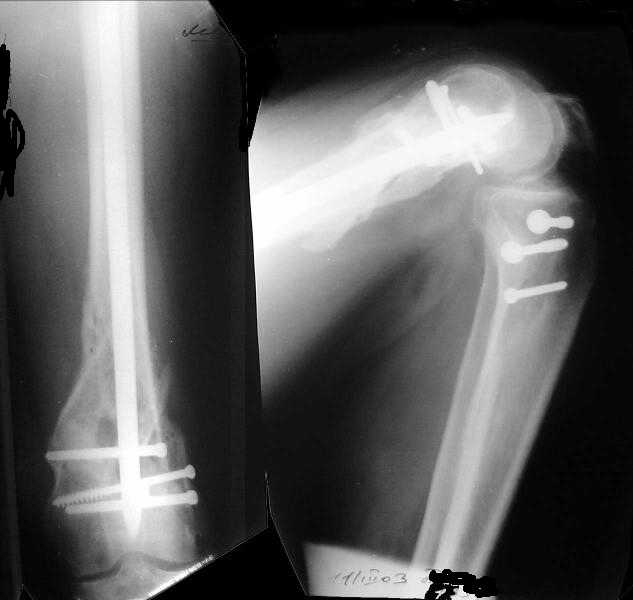

1

2

I attached an example of C2 fracture with result of the same technique in 5 months.